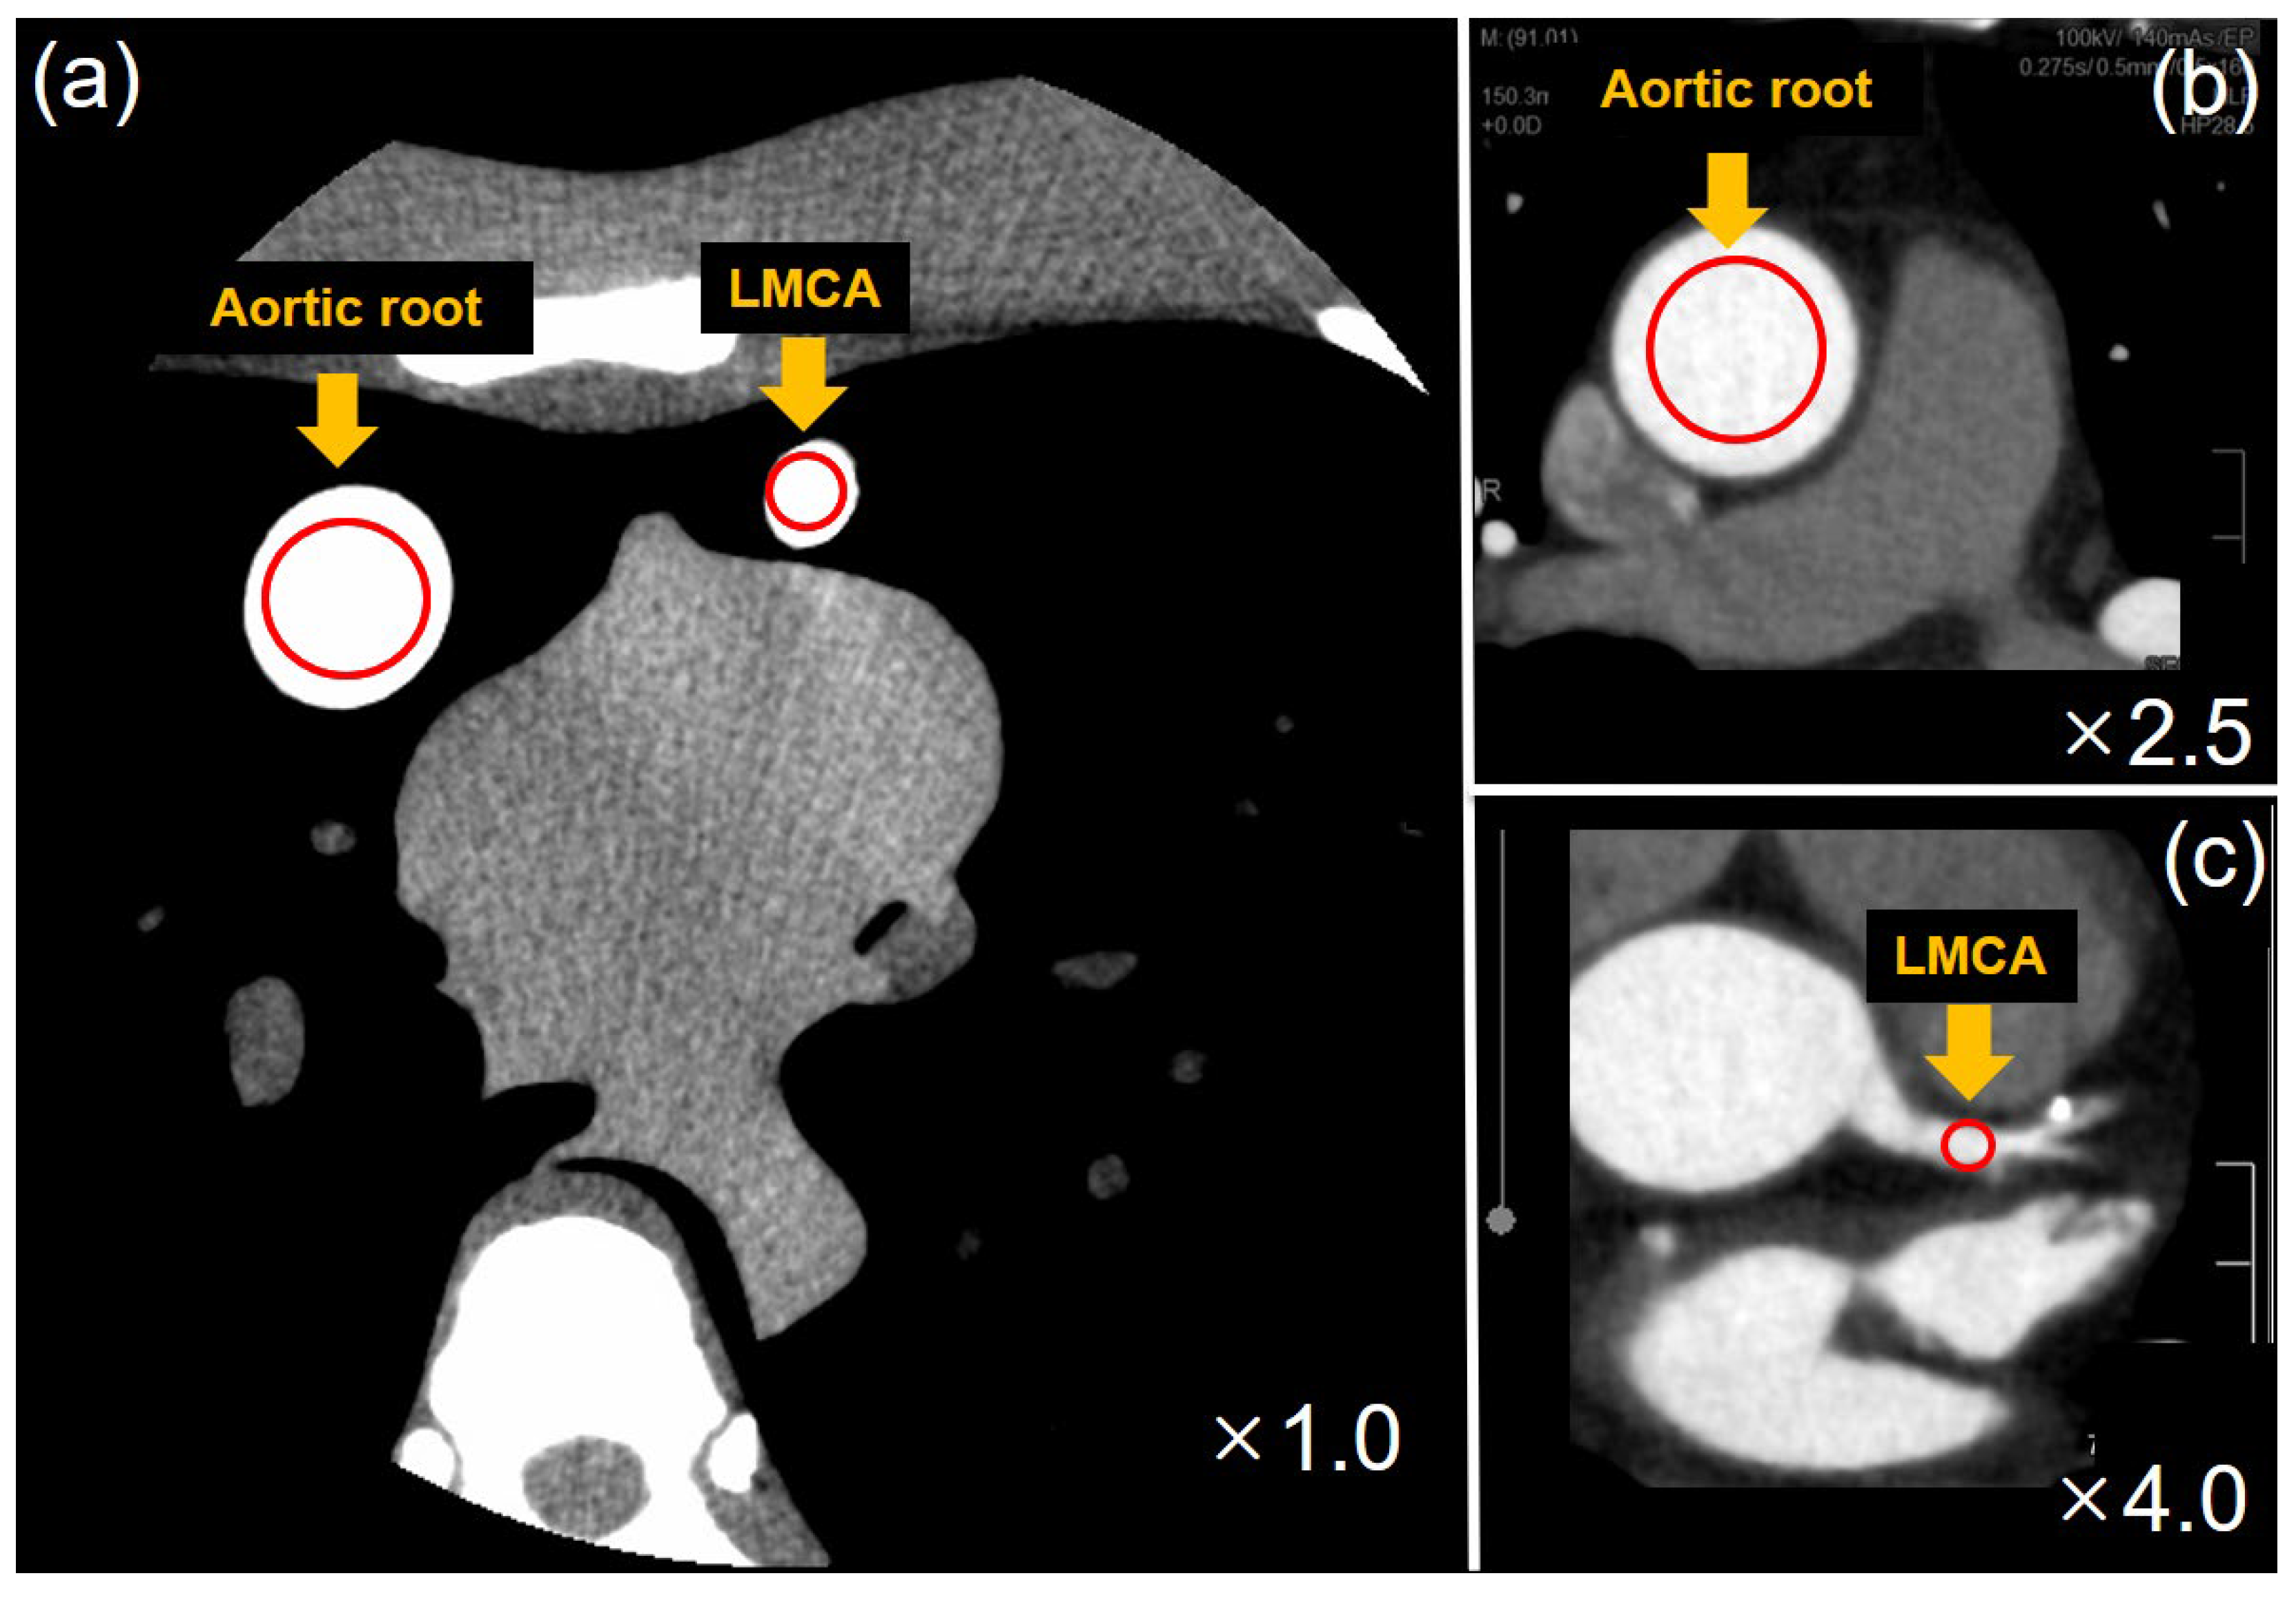

2.5. Image Analysis